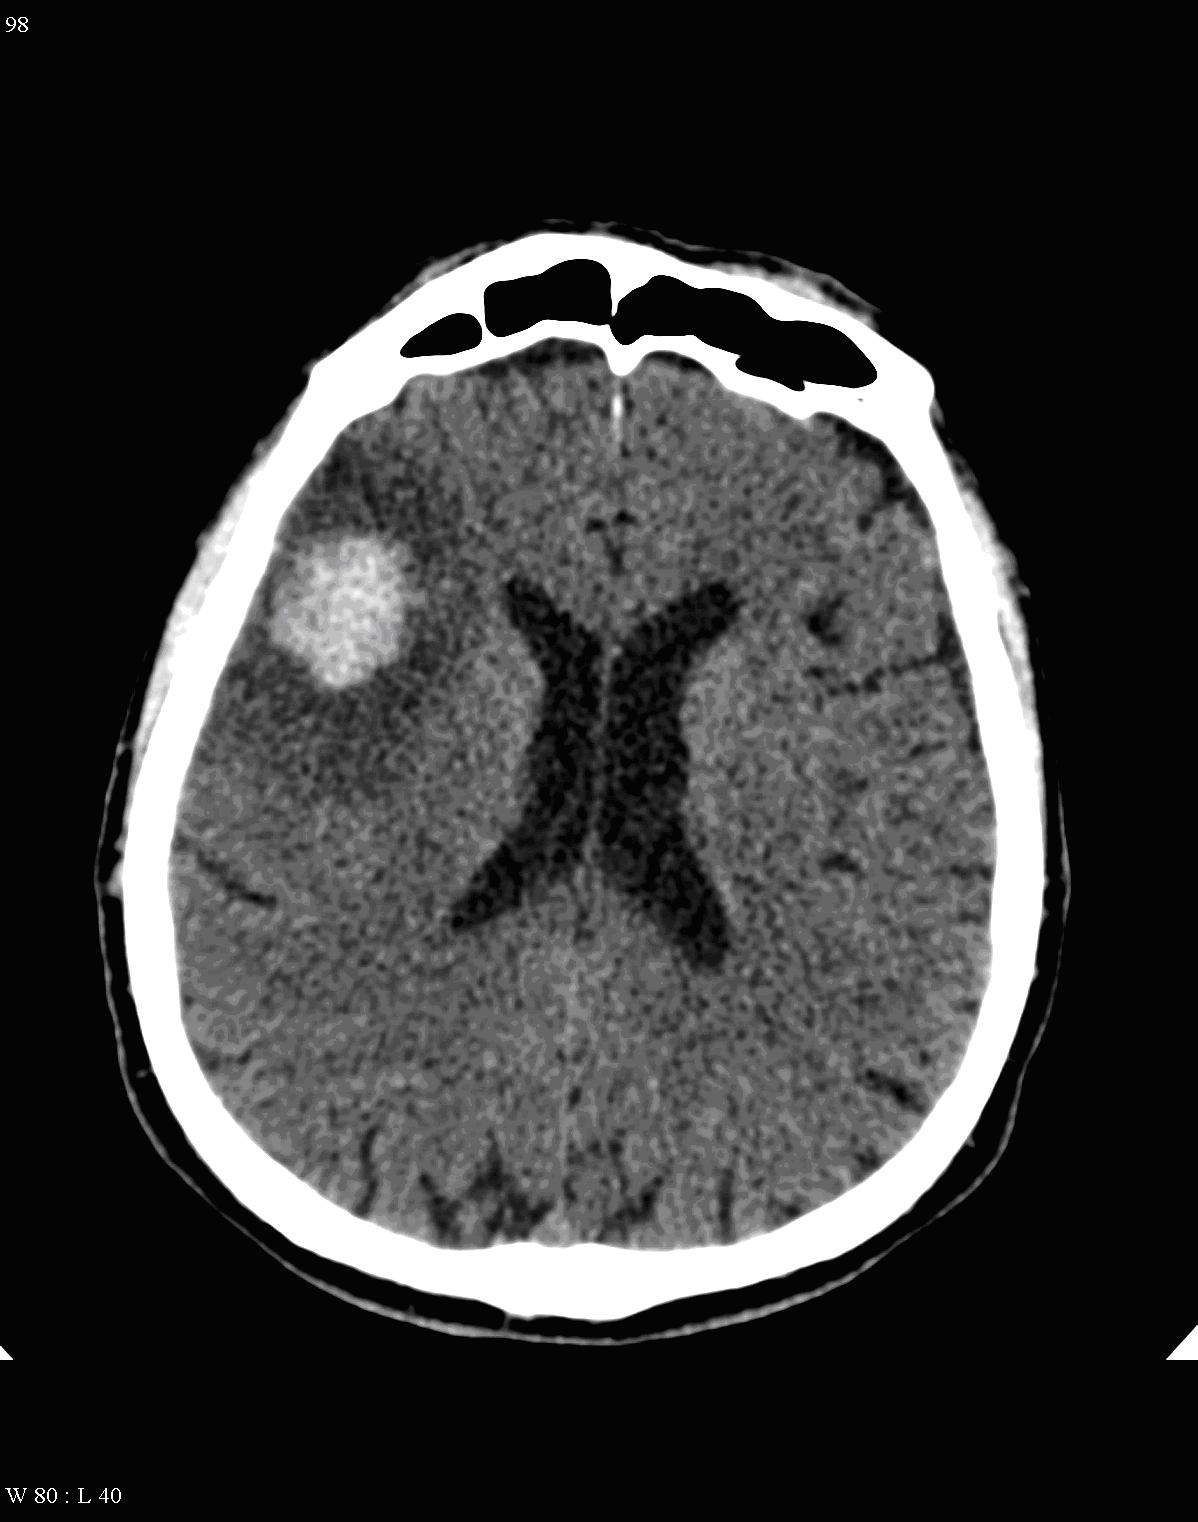

Fresh hemorrhage on CT appears hyperdense, therefore hemorrhagic stroke and subarachnoid bleeding can be promptly diagnosed with CT examinations.

Hemorrhagic infarcts make up 15% of strokes. The underlying cause is usually hypertension, but vascular malformation, aneurysm rupture, cerebral amyloid angiopathy, tumor bleeding and the hemorrhagic transformation of ischemic infarcts can all lead to cerebral hemorrhage. Moreover - as a rather common cause - patients with coagulopathies (mostly the ones receiving antithrombotic therapy) can also suffer hemorrhagic stroke.

Parenchymal hemorrhage most often occurs in patients with hypertension, after malignant hypertensive states. The initial localization for its occurrence is at the basal ganglia (putaminal-claustral hemorrhage) that can extend into the ventricles or to the subarachnoid space. The mean age of these patients is usually younger than that of the ones with ischemic infarcts.

On CT images acute bleeding always presents as hyperdensity. (One has to keep it mind that hyperdensity of the blood is affected by the hematocrit levels, hence making the diagnosis more difficult.) Intraparenchymal blood is dominated by a destructive appearance (mass-effect) and it is surrounded by hypodensity as a sign of perifocal edema. It often breaks into the ventricles. In patients lying in a supine position they collect (sediment) at the occipital horn of the lateral ventricles, creating a hyperdense liquid-to-liquid levels. Later on, the density of blood decreases and shows a peripheral ring or rim-like contrast enhancement without mass-effect.

Metastases:

The most common primary tumors that metastasize to the brain are: bronchus carcinoma, breast cancer and renal cancer. A so called early metastasis is especially typical for bronchus carcinoma, when the primary broncus carcinoma is still unknown.

Small metastases can produce very extensive edemas. Multiplicity is common. Due to the consequential blood-brain barrier disorders their contrast enhancement is very intense.